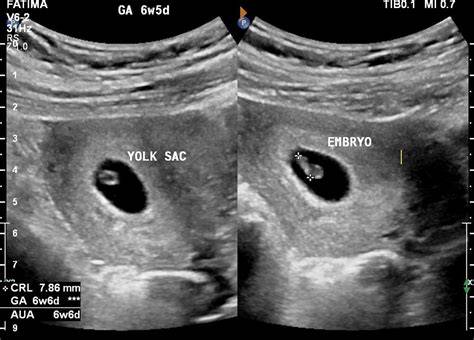

5. Early Pregnancy Scan: Why It’s Essential by Dr. Ekta Mishra

An early pregnancy scan is a critical clinical decision point.

This session explains why missing details here can change outcomes.

You will learn to:

• Confirm intrauterine pregnancy accurately

• Assess gestational age and fetal viability

• Rule out ectopic pregnancy early

• Detect early pregnancy complications confidently